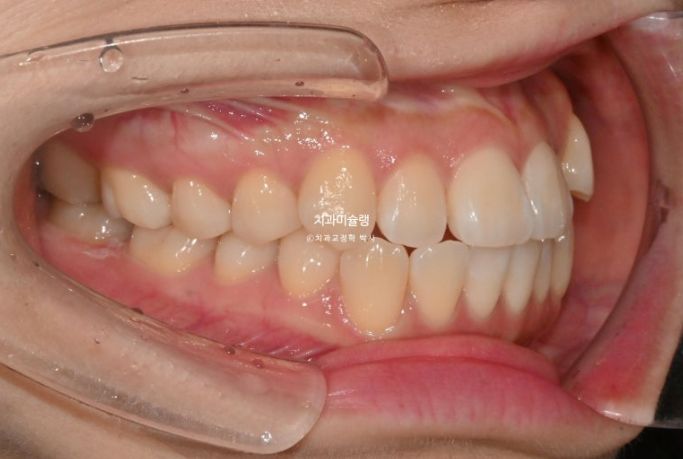

25년 3월부터 8월까지 첫세트 14개 장치를 모두 낀 후 모습입니다.

25.08

덧니 개선을 위한 고무줄 처방이 함께 들어갔으며, 메탈 고리는 고무줄 거는 고리를 치아에 붙여놓은 것 입니다.

반대교합은 해소가 되었지만 아직 중철치 - 측절기간 단차가 보이는 상태입니다.